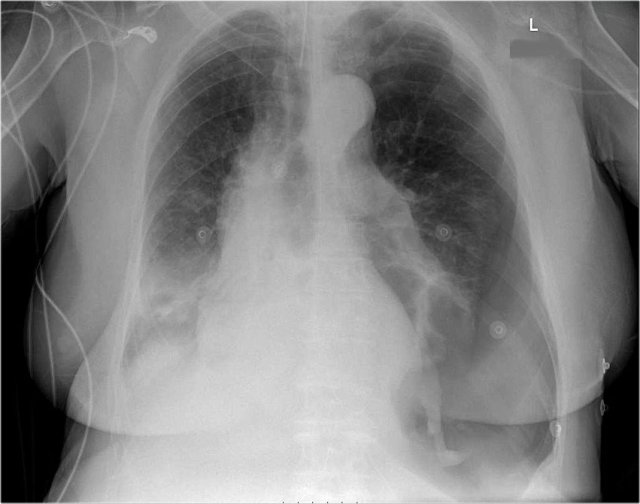

Pericardial effusion

Whenever we encounter a large heart figure, we should always be aware of the possibility of pericardial effusion simulating a large heart.

On the chest x-ray it looks as if this patient has a dilated heart while on the CT it is clear, that it is the pericardial effusion that is responsible for the enlarged heart figure.

Here another patient who had valve-replacement.

Notice the large heart size.

There is redistribution of the pulmonary vessels which indicates heart failure.

Continue with the CT.

The CT-image shows a large pericardial effusion.

Always compare these post-operative chest films with the pre-operative ones.